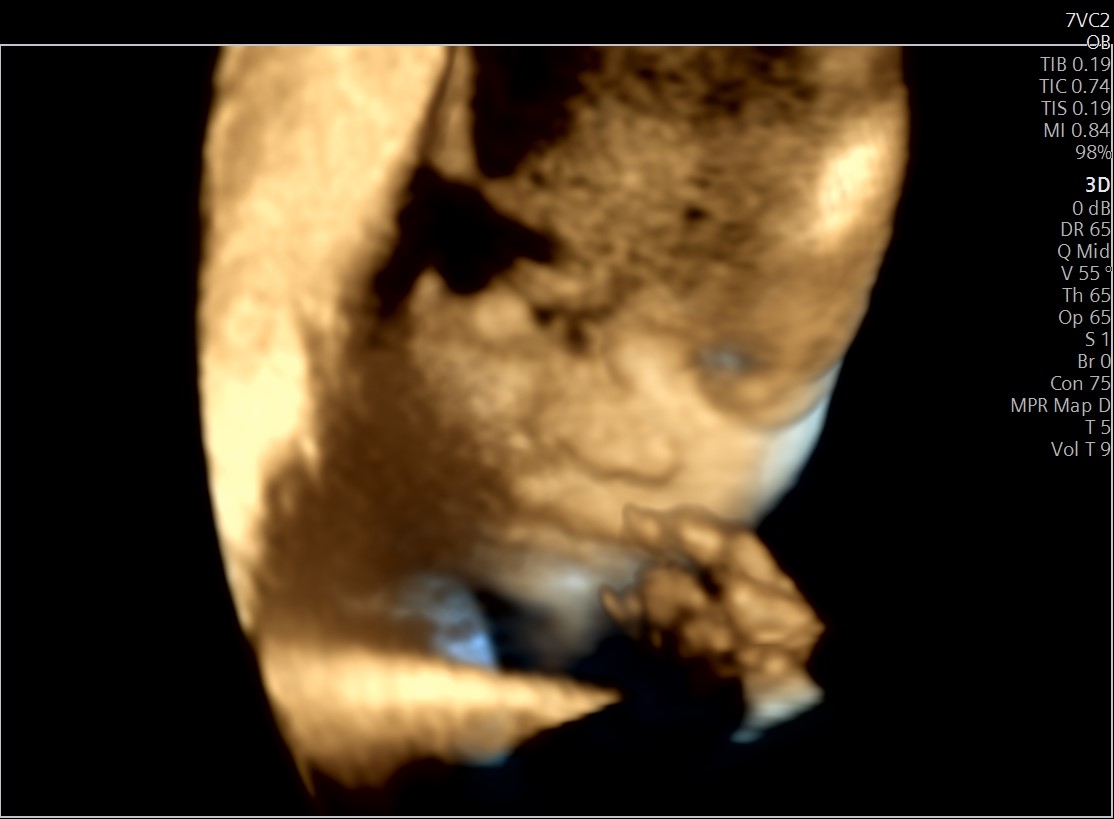

3d/4d echo

Je hoort en ziet het tegenwoordig overal! Een 3d en 4d echo. Mochten jullie in de zwangerschap al willen weten of jullie kindje meer op mama of papa (of grote broer of zus) lijkt dan is deze echo wat voor jou. De ‘leukste’ termijn voor een 3d en 4d echo is tussen de 26 en 32 weken zwangerschap. Op een 3d echo zul je jullie kindje in 3d kunnen zien. Met de 4d echo zijn deze 3d beelden live te zien. Alle dames die bij Lotus onder zorg zijn krijgen een kortingscode voor deze echo.

In de gallery zijn echo foto’s van kindjes van 10 t/m 36wk te zien! Neem een kijkje op de website van Echostudio Moon.